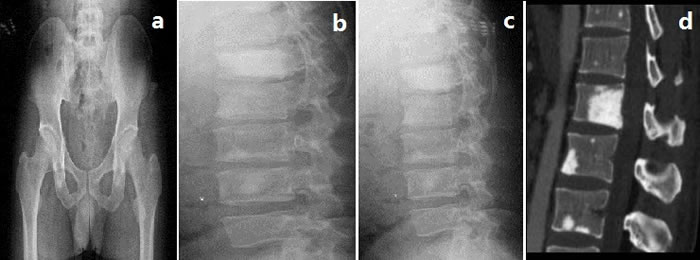

Splenomegaly, gynecomastia and enlarged axillary lymph nodes were confirmed by sonography. CT-angiography disclosed occlusion of the left internal carotid artery and disappearance of the left intra-cranial internal carotid artery (Figure 1). Brain magnetic resonance imaging (MRI) showed multifocal infarction beside the left lateral ventricle (Figure 1). A skeletal radiographic survey and computed tomography (CT) scan revealed multifocal sclerotic bone lesions in the thoracolumbar vertebrae and pelvis (Figure 2). On neurologic examination and nerve conduction studies, distal sensorimotor polyneuropathies were noted in his limbs. Bone marrow aspirate and biopsy gave no evidence of plasma-cell dyscrasia, and Bence Jones protein was negative in the urine. Immunofixation electrophoresis test did not detect monoclonal protein in the serum and urine for the first time. One week later, however, we repeated the serum protein and immunofixation electrophoresis in another laboratory and this time the presence of monoclonal protein (λ-light chain in the γ region ) was detected (Figure 3).

Figure 2: Skeletal radiographic survey and computed tomography (CT)

Sclerotic bone lesion may be a common feature of POEMS syndrome. From the data reported by Dispenzieri et al. [3], 96 of 99 patients (97%) diagnosed as POEMS syndromes in their hospital presented at least one abnormality detected on radiographic bone survey, including sclerotic and/or lytic lesions. Similarly, our patient also showed multifocal sclerotic bone lesions in the thoracolumbar vertebrae and pelvis. The pathogenesis of osteosclerosis in POEMS syndrome is still obscure. One study reported that the lytic lesions of myeloma are seemed to be mediated by the stimulation of osteoclasts by some cytokines, like IL-1β and TNF-α [9]. Thus, it is supposed that the osteosclerotic lesions might be resulted from an unbalance of osteoblast and osteoclast cell activities because of several cytokines. Moreover, platelet-derived growth factors, a kind of cytokines known to stimulate osteoblasts, are thought to be responsible for the diffuse fibrosis and osteosclerosis in agnogenic myeloid metaplasia and other myeloproliferative disease [10, 11], which might also account for the sclerotic bone lesions in POEMS patients.